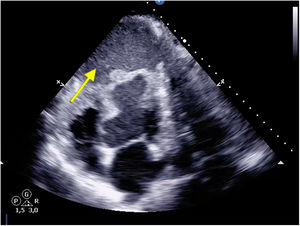

After 1 week on the urgent 0A waiting list, hemodynamic instability required an increase in pharmacological support, with transthoracic ultrasound revealing the rupture of the contained apical hematoma (Fig. 2, yellow arrow). Given the presence of refractory hemorrhagic shock despite measures, emergency surgery was scheduled to control the bleeding. However, coincidentally, a compatible organ became available for our patient, and a heart transplant was ultimately performed.